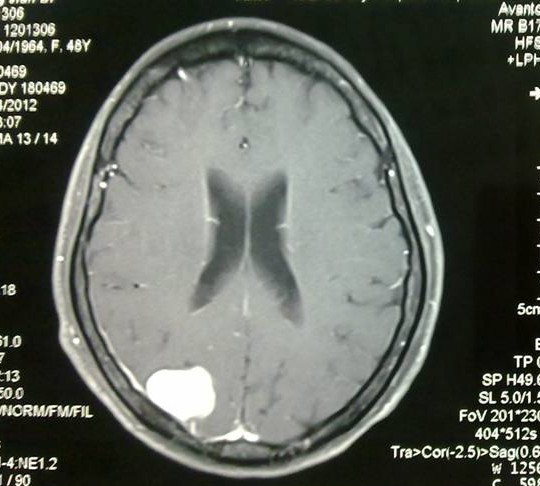

术前MRI增强成像,肿瘤位于右顶叶,与矢状窦较为接近,而术中实际情况是有一部分肿瘤组织直接贴在矢状窦壁上,手术难度比术前预计的更大。